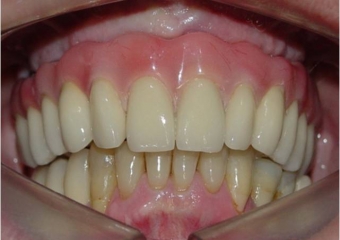

Sorriso final, do caso terminado em Julho de 2009

Imagem final